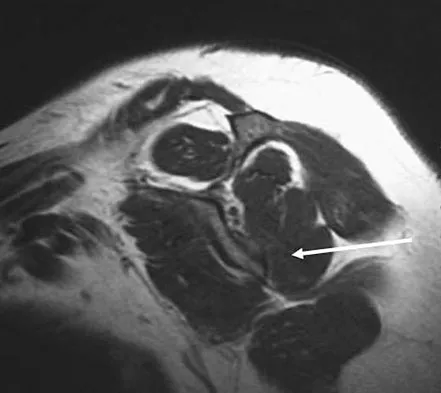

A 12-year-old boy has severe left shoulder pain after being struck by an automobile. A chest radiograph, AP and lateral radiographs, and a CT scan with three-dimensional reconstruction of the scapula are shown in Figures 38a through 38d. Management should consist of

Explanation